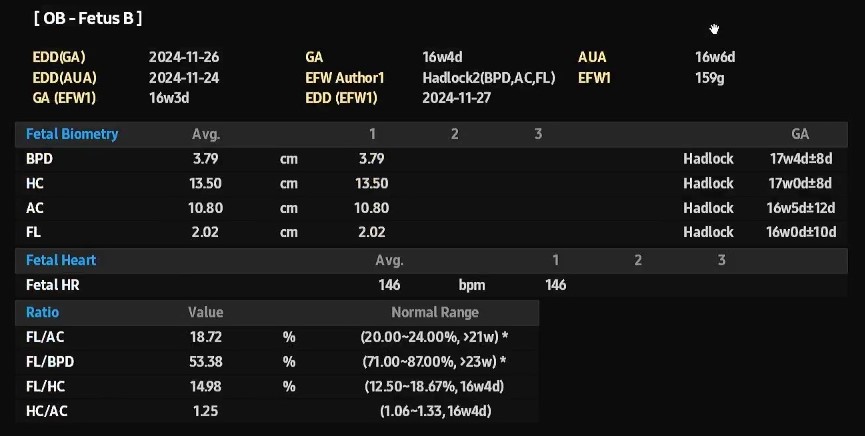

쑥쑥이는 161g, 쭉쭉이는 159g으로 둘의 차이는 1.17%로 주수에 맞게 아주 잘 크고 있었어요.